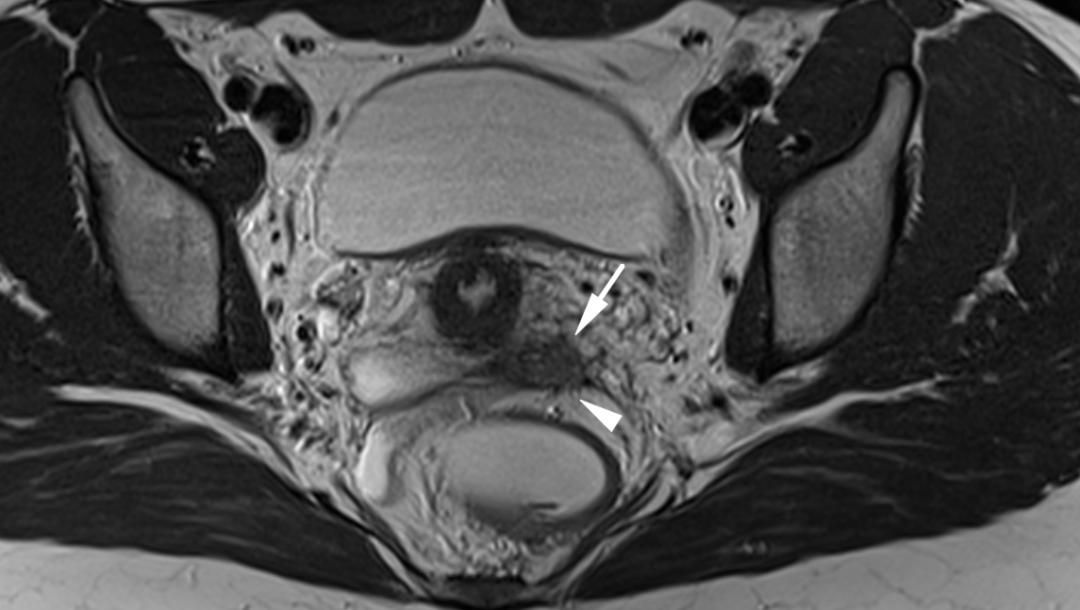

T2WI 矢状位显示子宫颈右后方结节样低信号,其内微小高信号结节,边缘毛糙,累及右侧子宫骶韧带、阴道后穹窿、直肠壁; T1WI 轴位可见小结节高信号,提示出血。

子宫内膜异位至阴道-直肠生殖隔,T2WI 轴位和矢状位显示阴道生殖隔结节样高信号,边缘星芒状,同时显示道格拉斯窝积液。